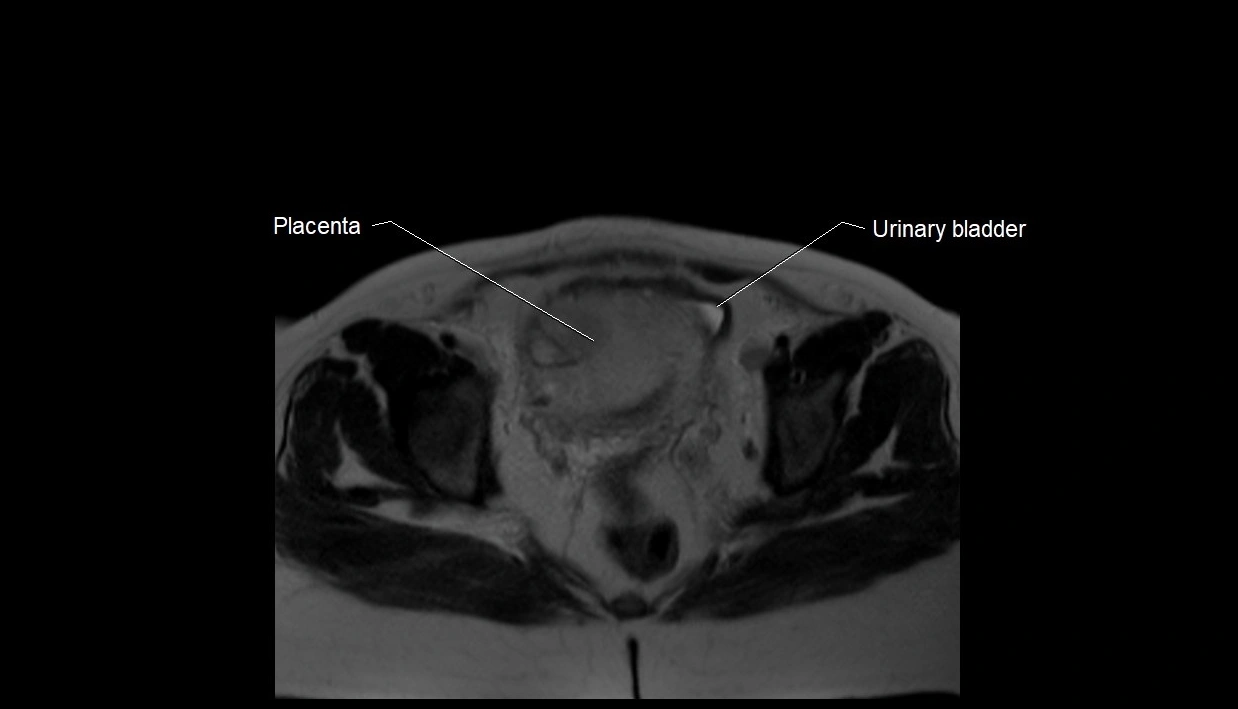

MRI Appearance

T2 HASTE (T2 GRE):

• Amniotic fluid shows very bright hyperintense signal

• Provides natural contrast against fetus and placenta

• Small particles (vernix) may appear as scattered hypointense foci within bright fluid

T1 GRE:

• Amniotic fluid shows low signal intensity (dark)

• Hemorrhage, infection, or proteinaceous content may cause focal or diffuse high signal intensity

MRI image

image